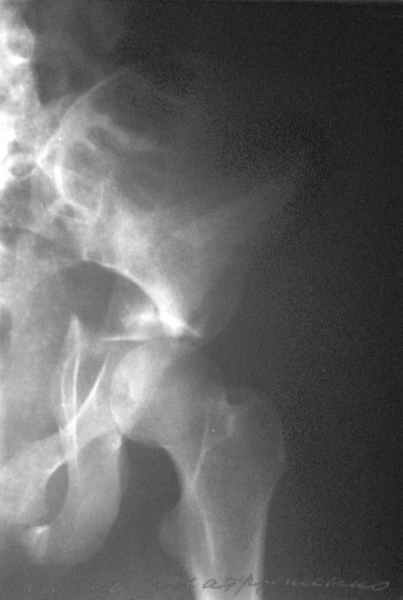

Посылаю схемы и 3D реконструкцию подобного повреждения. Называется он полным высоким двухколонным переломом вертлужной впадины, а "переломы крыла и тела подвздошной кости" входят в это понятие.

Вариантов остеосинтеза много (можно и не оперировть, т.к. конгруентность при таких переломах как правило сохраняется)